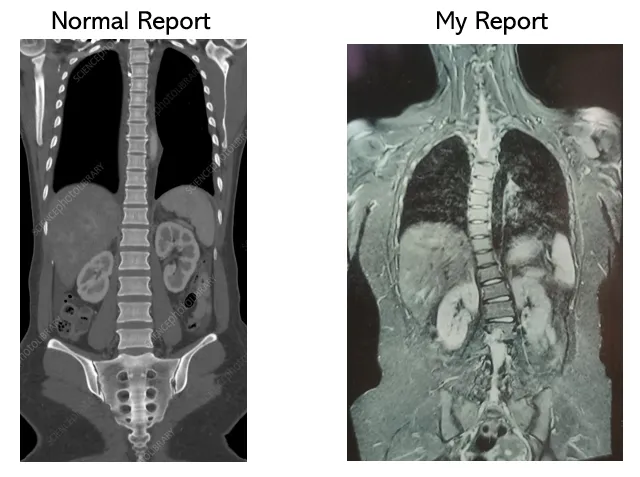

Unable to understand what caused the pain, I went to the SVS Medical College for a CT scan. The doctor looked very serious while taking the scan. As soon as I came out, he asked two questions: "Do you have this back pain since birth?" and "Did you undergo any major accident recently?". I denied both. He was confused and said, "Only these two conditions could explain the damage to your spinal cord that is visible in the scan.". I informed about all this to my family members and we went to multiple doctors for consultation. Every doctor was surprised that how can the spinal cord change its shape without a major accidental injury! I am attaching the images of my CT Scan report here along with normal healthy report for comparision.

As a matter of fact, I neither felt this pain since childhood nor met with any accident. I don’t like traveling, sports, dance and any physical activity. I told the doctors that I don’t participate in any physical activities either. Every doctor had admitted that this sudden pain in my spinal cord is beyond their understanding and even the cure is beyond is their expertise because nobody knows when the pain is going to attack suddenly. My family members and myself came to the conclusion that this is purely Swami’s miraculous protection. We understood that Swami would have either taken all my pain for the last 25 years since my birth or He had saved me from a major accident that was destined to happen due to my bad karma. Both scenarios are too horrible to imagine. How can an ignorant soul like me ever comprehend how much pain and effort Swami takes on Himself for me so that I live a normal healthy life?